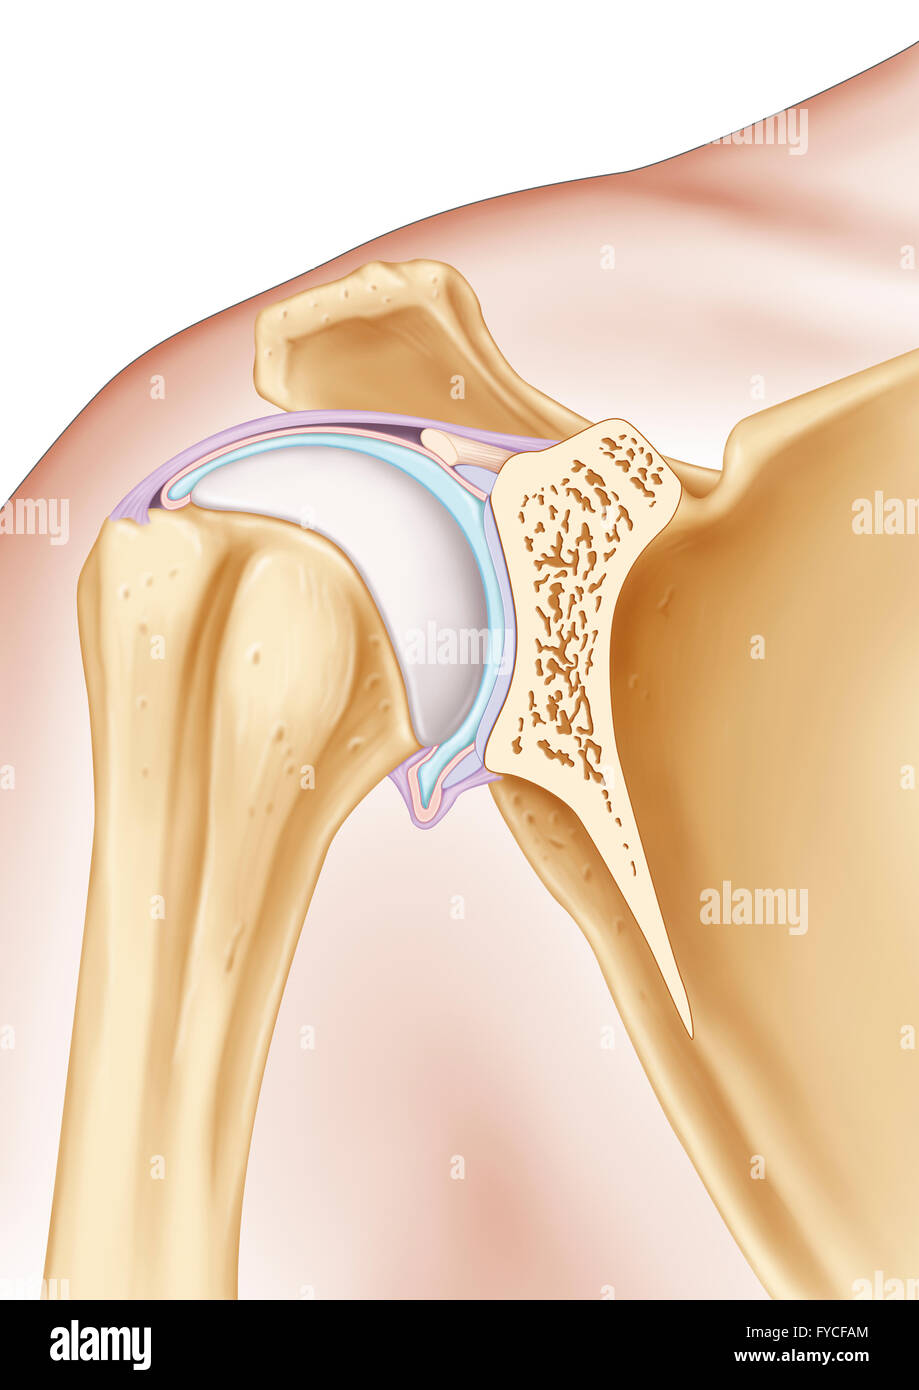

SHOULDER, ILLUSTRATION Stock Photohttps://www.alamy.com/image-license-details/?v=1https://www.alamy.com/stock-photo-shoulder-illustration-102923036.html

SHOULDER, ILLUSTRATION Stock Photohttps://www.alamy.com/image-license-details/?v=1https://www.alamy.com/stock-photo-shoulder-illustration-102923036.htmlRMFYCFAM–SHOULDER, ILLUSTRATION